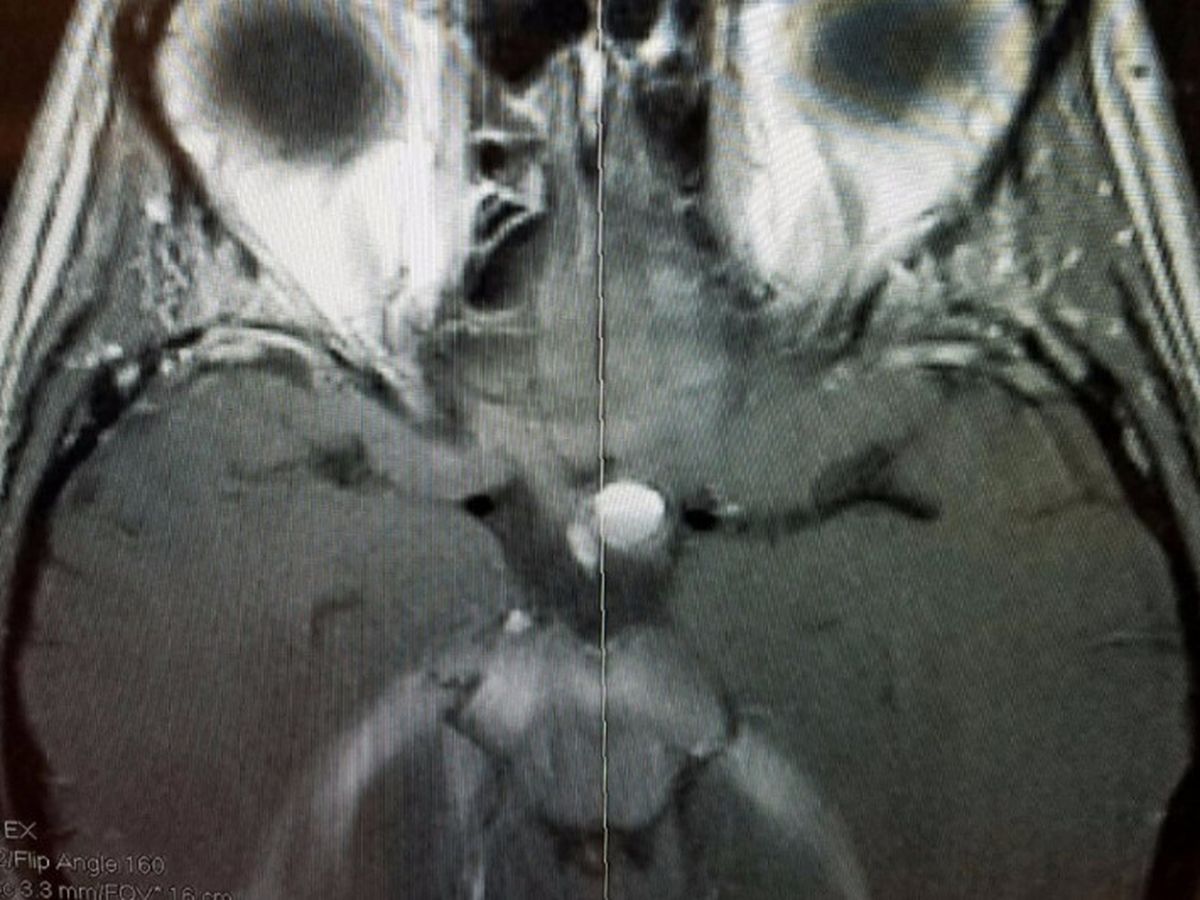

Hi my name is Monte. The pic you see is from the MRI of my sister Tina's head. The white circle in the center of the pic is what the Dr's think is a blood clot, but won't know for sure until they do surgery. For the last month she has been loosing sight in her one eye because it has been putting pressure on her optic nerve. It took multiple tests, and appointments with different specialists to figure out what was causing her to loose sight. The Dr's initially said it was a lesion on her brain, but didn't know exactly what was causing it. It could have been caused from a disease, trauma, or a tumor. Fortunately they don't think it is any of those things, but won't know for sure until they do surgery. She goes in this Wednesday on November 30th to have surgery were the Dr's will have to open up her skull to remedy the issue. They aren't sure if her full sight will return. My sister Tina is a single mom of two, who works two jobs already just to try to make ends meet. Thankfully she has insurance through her work that will cover 80%, but she will have to pay the other 20%. I don't know exactly how long she will be out of work to recover, but the money raised will go towards her medical bills and loss of income due to not being able to work. Honestly I dont know if the goal amount will be enough if it is reached, but anything will help.